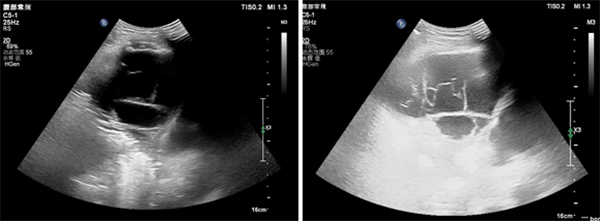

据悉,该患者因严重呼吸困难、无法平卧,需携带氧气瓶紧急就诊。我院超声检查显示,患者胸骨旁偏右侧存在范围约 8.7×7.4cm 的包裹性积液,内有多发分隔,且已向后挤压心脏,穿刺难度极大。王金萍结合多年临床经验,经全面评估后判断患者具备穿刺可行性,随即制定个性化治疗方案。

术中,王金萍借助超声实时动态引导技术,清晰追踪针尖完整行进轨迹,精准避开血管、神经等重要器官。在全程可视化监测下,团队顺利为患者抽出270mL暗红色粘稠液体,术后患者包块基本消失,呼吸困难症状即刻缓解,成功撤掉氧气瓶,且未出现气胸、出血等并发症,恢复情况良好。